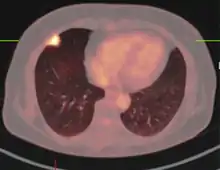

Imágenes

El aspecto de un tuberculoma en el diagnóstico por imagen puede variar en función de la composición y la edad de la masa. Pueden aparecer como lesiones no caseificantes o sólidamente caseificantes. Inicialmente, los tuberculomas aparecen hipodensos en la tomografía computarizada (TC) con un edema circundante significativo. El "signo del blanco" es patognomónico de tuberculoma en la TC, con una masa nodular anular y calcificación central. El aspecto anular característico se debe a la falta de irrigación sanguínea en el núcleo necrótico central que se visualiza con el contraste inyectado. A veces se observa una zona central hipodensa en lugar de calcificación. Al considerar otras posibles masas intracraneales en un diagnóstico diferencial, como la cisticercosis, el absceso piógeno y las lesiones neoplásicas, el tuberculoma puede identificarse por su mayor tamaño (>2 cm), edema y borde irregular.

La resonancia magnética (RM) es otra modalidad de imagen útil para diagnosticar y caracterizar los tuberculomas, especialmente la necrosis caseosa sólida en la que se observan 3 zonas de intensidad variable.